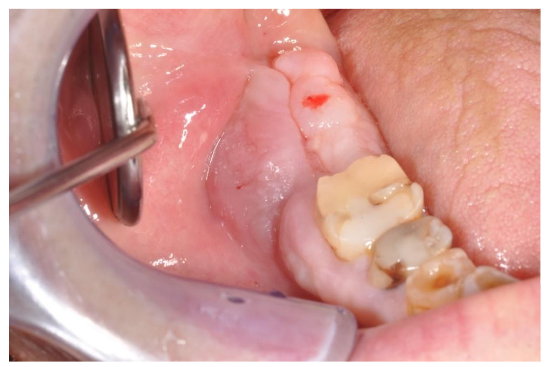

Despite his bad conditions the patient was independent and conscious of his health conditions and he required the resolution of the pain to live the last years without that problem. The oral lesion had a vegetative aspect with exophitic growth of the gingival mucosa associated with bone osteolysis and osteonecrosis of the right mandible. The lesion had an important opening along the edge of the mandible into the exophitic tissue (image 2) that connected the osteolytic lesion with the oral cavity: this gap allowed to a continuous bacterial invasion with frequent infections.